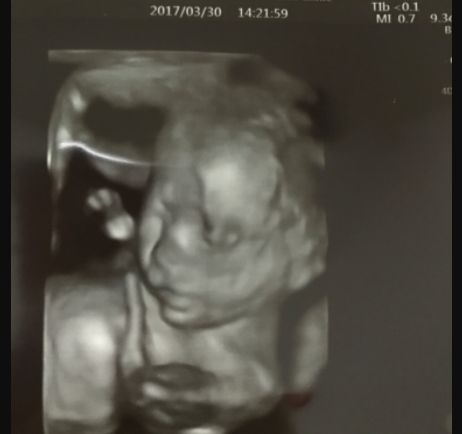

20週0日(20w0d・男の子)|01れい さん(36歳)

エコー写真撮影時のエピソード:

お腹がポコポコ動くようになり、元気いっぱいでーす!

家族みんなが望んでいた男の子だったのでとっても喜んでくれました!

生まれてくるの、みんなとっても楽しみにしているヨ!ずっと元気いっぱいでいてね!

お母さんは毎日赤ちゃんの動きにびっくりしていますが、お医者さんには、いつも元気だね!と言われてとても嬉しいです!